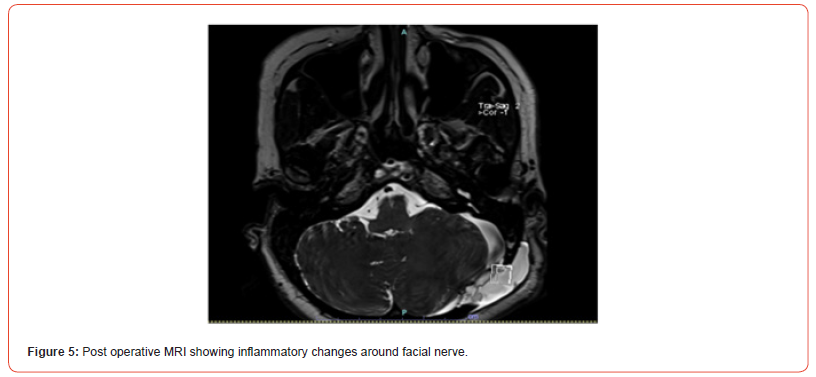

symptomatic postoperatively. Repeat MRI done shows pseudomenigocele

and inflammatory changes around facial nerve.

Patient was started on high dose steroid there was gradual improvement

in the facial weakness and gait. Pure tone audiometry

showed bilateral minimal hearing loss. No retraction injury

to auditory nerve. (Figure 4 & 5),